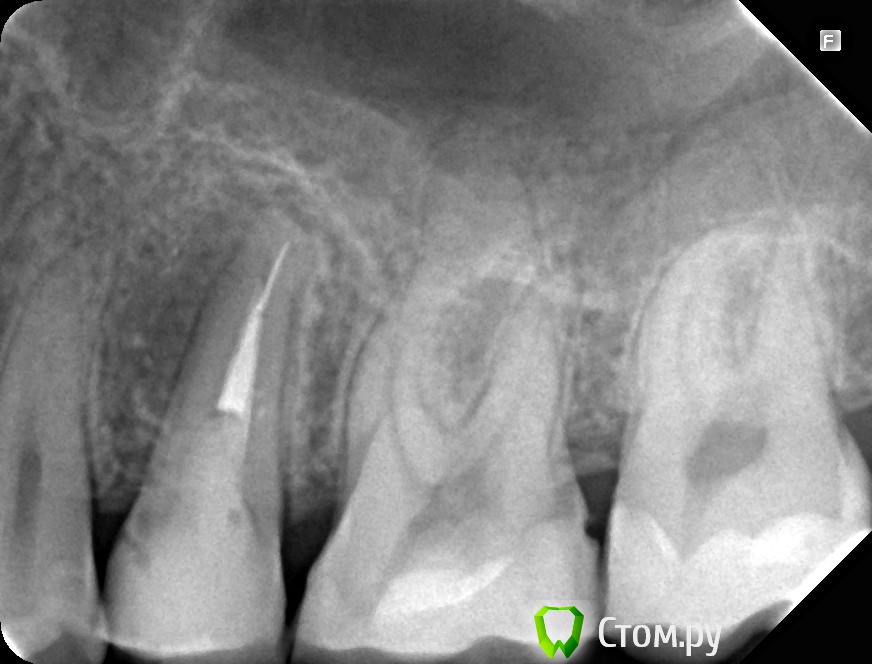

Юлия Арт Опубликовано 14 марта, 2014 Поделиться Опубликовано 14 марта, 2014 (изменено) День добрый, уважаемые специалисты!Месяц назад у верхней 5-ки обнаружили воспаление, врач сказал зуб удалять так она вбоку и ,по его мнению, в канале трещина.Вчера хирург сделал панорамный снимок, и отказался удалять зуб, сказав что нет причины... Сегодня пошла к нему опять-сделали маленькое фото того зуба, воспаление меньше стало, но что дальше делать? посоветуйте, пожалуйста. Можно ли пока оставить этот зуб в покое, надо другими 5-ю штуками заниматься, которые болят сильно. 2 снимка, один сделан в феврале. второй-сегодня, март Изменено 14 марта, 2014 пользователем Юлия Арт Ссылка на комментарий